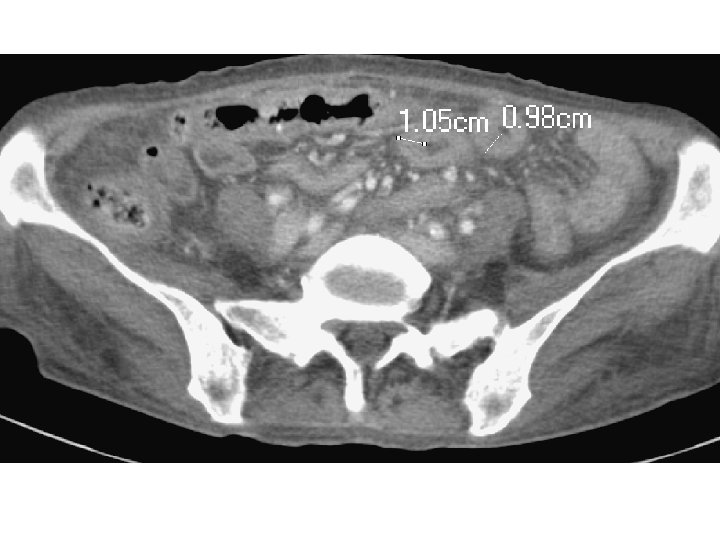

Double halo sign or target sign l Double halo sign = either a higher-attenuation outer ring (muscularis propria) + inner ring of gray attenuation or a higher-attenuation inner layer (submucosa) + outer ring of gray attenuation. Differential Diagnosis — l Idiopathic inflammatory bowel diseases, vascular disorders, infectious diseases, and radiation damage. The uncommon diagnosis in which this pattern occurs is malignancy.

Comb sign l Higher-attenuation l To of vasa recta differentiate active inflammatory condition from lymphoma and metastases, which tend to be hypovascular.

D/D for chronic lower abdominal pain X BWL X double halo X comb sign GI Gyn GU Other Malignancy IBD Bowel obstruction Infection (diverticulitis, gastroenteritis, infectious colitis, peritonitis, mesenteric lymphadenitis) Malignancy PID Tuberculous salpingitis Pelvic adhesion Malignancy (eg. lymphoma) Systemic inflammatory disease (eg. CTD, vasculitis) Metabolic disease (eg. DM, hyperthyroidism, adrenal insufficiency) Mesenteric ischemia Neuro Malignancy